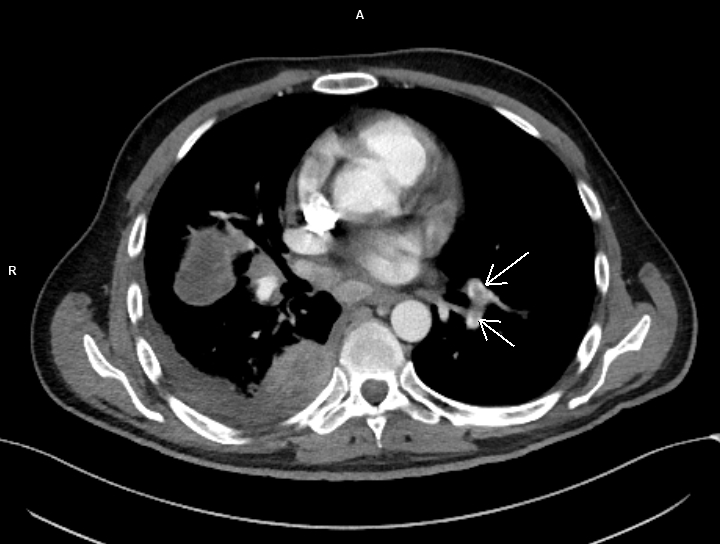

Figura 1: axial CT în timp arterial

Discuţie caz nr 99: pacientul s-a prezentat în urgență și a fost trimis la examinarea CT cu suspiciune de trombembolism pulmonar. Examinarea CT efectuată toracic care a surprins și o parte din abdomenul superior evidențiază trombembolism pulmonar acut stâng la nivelul arterei intermediare cu evoluție și la nivelul arterelor segmentare și subsegmentare precum și tumoră renală stânga de pol inferior cu aspect de carcinom cu celule clare (Grawitz) și determinări secundare pleurale drepte.